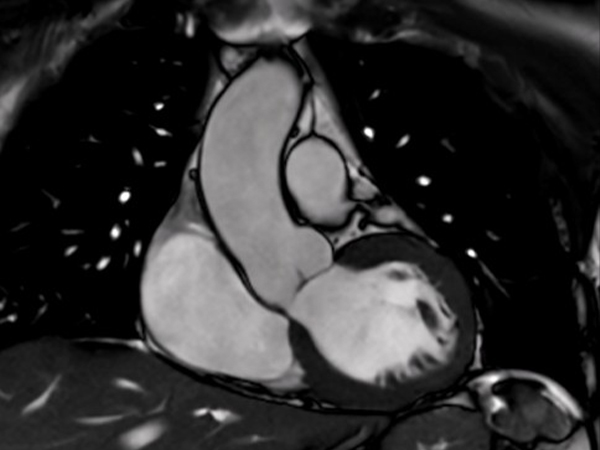

Comprehensive Cardiac with SmartSpeed Precise